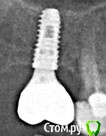

Наталия1966 Опубликовано 6 октября, 2019 Автор Поделиться Опубликовано 6 октября, 2019 (изменено) Да мне кажется, что тему закрыть можно. Топикстартер с тем же успехом может сама с собой говорить.Ну, вообщем, да, можно закрыть. Но мне было бы интересно дождаться результата установки. Все не так просто, как нам кажется с первого взгляда и случаи разные бывают. В принципе, в принципе... выдавливание гноя помогло и очень. Сегодня я проснулась и первым делом ощупка языком места - десна абсолютно ровная, потом побежала к зеркалу - гнойник ушел на его месте еще не совсем срослось и мягкий небольшой провальчик в месте гнойника, то есть заживает! Я сама еще пальцем слегка помассировала все вокруг от зуба до зуба -выдавилась еще капля гноя и все совсем опало. Десна розовая, ничего не болит. Заодно промассировала другой имплант, где мне в воспаленье вкрутил врач, он не болит, но нажим на десну и отпускание сильную пульсацию без боли вызывало. Там обмассировала и вот результат - десна лучше прилипать стала и пульсация исчезла! Вывод - никогда не надо торопиться, принимать поспешных решений. Если есть регламент - выжидать, значит нарушать его не надо 9 октября будет ровно 4 месяца. А на таком расщеплении гребня, видите, только только нормализовалось и то с вмешательством врача по десне. Нижние зубы не могут сливать сами гной как верхние, где он просто оттекал бы вниз. Тут вероятно он копиться в челюсти и не может сам исчезнуть. Вот такие пироги. Всем спасибо за внимание и добрые пожелания. Вот этим двум имплантам в июне ровно год был. Снимок в конце августа сделали. Одиночному верхнему год в ноябре будет. Изменено 6 октября, 2019 пользователем Наталия1966 Ссылка на комментарий